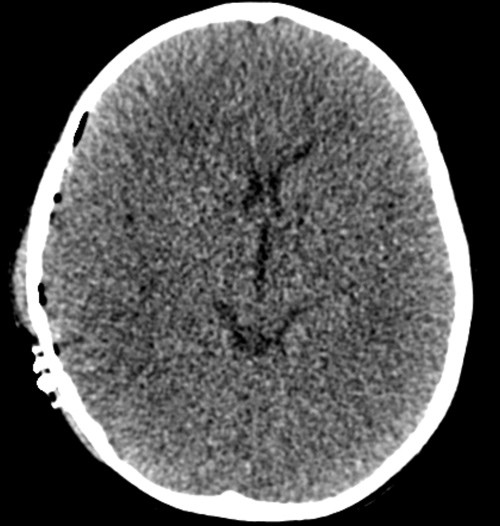

I akuttmottaket åpnet han så vidt øynene på sterke smertestimuli, laget kun enkelte lyder og hadde målrettede avvergebevegelser, dvs. Glasgow Coma Score 9 (pediatrisk GCS-versjon). Etter en rask klinisk undersøkelse ble det utført CT-undersøkelse av hodet. Den viste et stort epiduralt hematom på høyre side, med masseeffekt og midtlinjeoverskyting (bildet til venstre). Man så også det som blir kalt «swirl sign», som indikerer en pågående og kraftig blødning (grønn pil) (2). På vital indikasjon ble han tatt direkte til Nevrokirurgisk operasjonsstue, der det ble gjort en kraniotomi med evakuering av hematomet. Ny CT-undersøkelse av hodet dagen etter viste pene postoperative forhold (bildet til høyre).